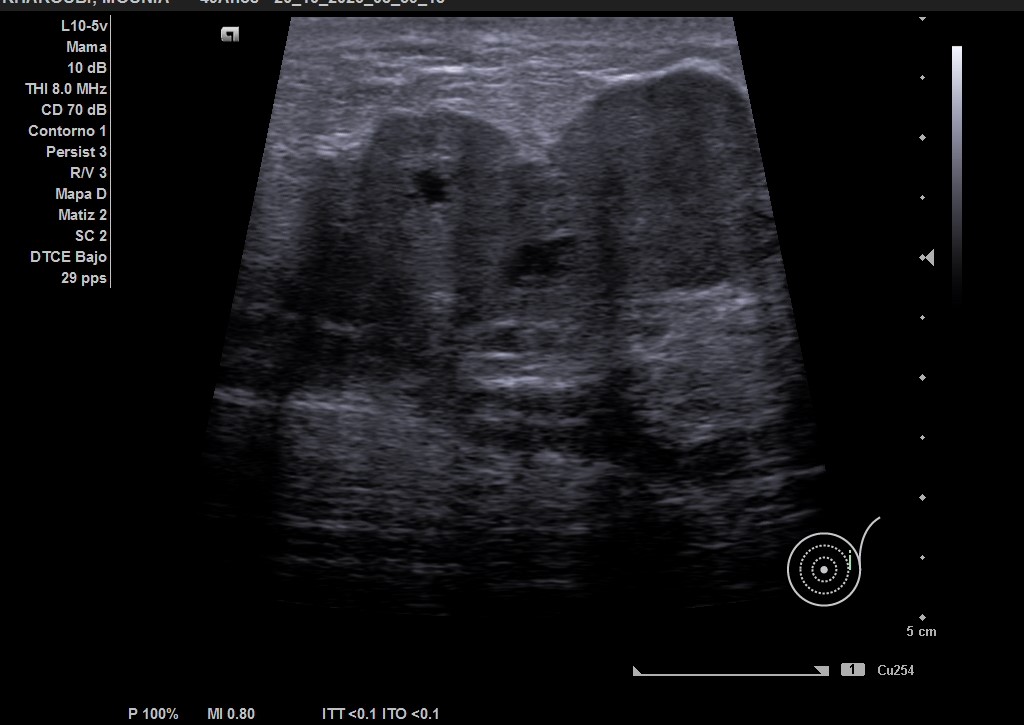

Ecografía: mama izquierda se observa tumoración hipoecogénica lobulada en cuadrante superior externo de aproximadamente 4 cm, heterogénea, que capta al Doppler color y dos adenopatías de aspecto reactivo en axila homolateral. Imagen sospechosa de malignidad.

Mamografía bilateral mama izquierda: masa mal definida de al menos 5 cm de diámetro, asociada a un engrosamiento cutáneo y trabecular difusos. Hallazgo sospechoso de malignidad. Adenopatías axilares izquierdas.

Ecografía de mama hospitalaria: Se confirma en mama izquierda masa sólida palpable de al menos 56 mm, de contorno mal definido, sospechosa de malignidad. Se realizará BAG ecoguíada, y adenopatías axilares izquierda de aspectos patológico. PAAF de ganglio izquierdo dirigida por ecografía: Citología positiva para malignidad. Compatible con metástasis de carcinoma. Biopsia BA Tipo histológico: Carcinoma infiltrante. Grado histológico: Grado III, pobremente diferenciado.